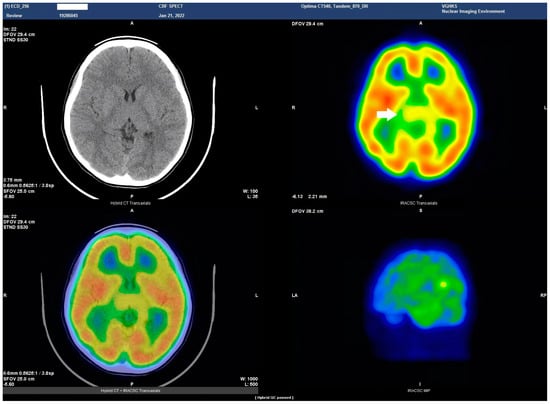

HSAN4 is a rare genetic disorder with a complex clinical presentation. Our hypothesis that the CNS might be implicated in this condition gained substantial support from the clinical manifestations observed in our patient. The presence of spasticity in her feet and a strong positive Babinski’s sign, which are characteristics commonly found in patients with upper motor neuron (UMN) lesions [16], prompted us to explore the potential involvement of the central nervous system (CNS) in HSAN4. To investigate this novel aspect, we employed Tc−99m ECD SPECT imaging for assessing cerebral blood flow and revealing perfusion deficits within the brain [23]. This study represents the pioneering visualization of brain perfusion abnormality in an HSAN4 patient, and the findings are nothing short of groundbreaking. Our Tc−99m ECD SPECT imaging revealed multiple areas within the CNS with perfusion deficits. Notably, these deficits were observed in the cerebellum (Figure 2), thalamus (Figure 3), and postcentral gyrus of the parietal lobe (Figure 4 and Figure 5). These findings suggest that HSAN4 has the potential to affect not only the peripheral nervous system (PNS) but also the CNS, ushering in a new era in our understanding of this complex disorder. One of the most significant and intriguing aspects of our findings is the localization of these deficits in the postcentral gyrus and thalamus. These regions play pivotal roles in processing pain signals transmitted from the spinothalamic and spinoreticular tracts [24]. The spinothalamic and spinoreticular tracts are the central pathway for nociceptive signals, conveying pain information from the peripheral nervous system to the cerebral cortex. The former pathway originates from the dorsal root ganglia, traverses the dorsal horn of the spinal gray matter, proceeds to the ventral posterolateral nucleus of the thalamus, and finally reaches the posterior limb of the internal capsule. The latter tract also handles nociceptive signals, routing them to the thalamus and postcentral gyrus [25,26]. The perfusion deficits we observed in these crucial pain-processing areas offer a profound and novel perspective on explaining the pain insensitivity characteristic of HSAN4 patients. While previous research has primarily focused on the peripheral mechanisms of pain insensitivity, our study provides compelling evidence that the origin of this phenomenon might extend beyond the peripheral nervous system.

Another intriguing aspect of our Tc−99m ECD SPECT imaging results was the presence of a perfusion deficit in the right cerebellum, a region not commonly associated with pain processing but known for its diverse functions [27]. Previous studies have suggested that the vermis and deep cerebellar nuclei are associated with pain-related activation [28]. Furthermore, the cerebellum can distinguish between active and passive pain stimuli and is involved in pain anticipation [29,30]. This suggests that the cerebellum may play a cross-modal modulatory role in pain perception [31]. While further research is needed to fully elucidate the role of the cerebellum in pain processing, our findings indicate that this region might contribute to the complex puzzle of pain perception. The cerebellum’s involvement adds an intriguing layer to our understanding of HSAN4 and suggests that the condition’s impact on pain perception extends beyond the classic pain pathways.

Figure 2. Axial view of the Tc−99m ECD brain perfusion SPECT study. A decreased uptake in the tracer(Tc−ECD) can be observed in the right cerebellar hemisphere (arrow). Left upper panel, CT image; right upper panel, SPECT; left lower panel, the combined SPECT and CT images.